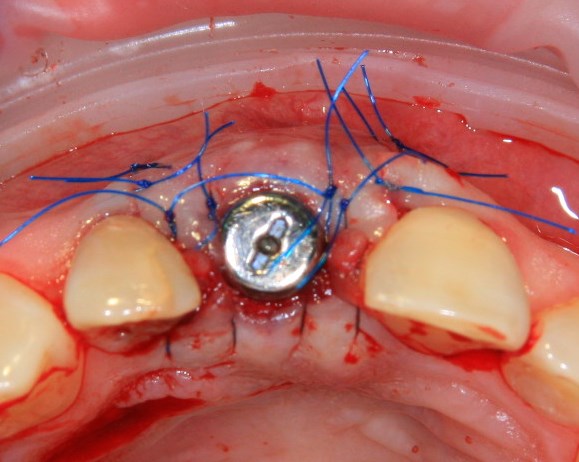

Немедленная имплантация — оптимальное решение в любой клинической ситуации